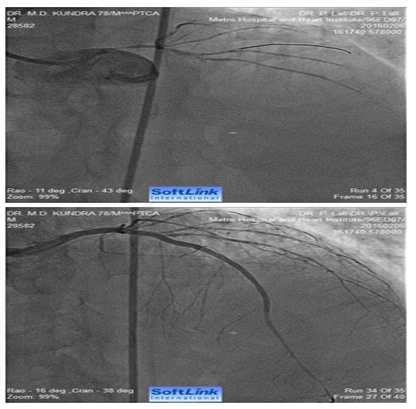

Figure 3 AP-cranial view. An 82 years old male presented with acute anterior wall MI. Coronary angiography revealed total occlusion of mid LAD. Fluoroscopy showed extensive calcification involving LMCA and LAD. The occluded segment was full of thrombus. LAD could not be opened-up despite repeated balloon inflations in progressively increasing sizes. The right panel shows fully opened-up LAD after ‘rota-stenting’ with a 1.25 mm burr and deployment of a 2.5 mm drug eluting stent.